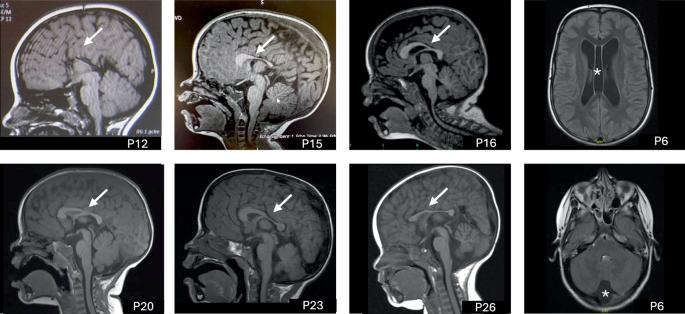

CCR4-NOT复合物在基因表达调控中起着至关重要的作用,其中包括CNOT3,这是一种突变时与神经发育障碍相关的亚基。本研究调查了来自42个CNOT3杂合变异家族的51例患者,旨在扩大对CNOT3相关神经发育障碍的认识,并探索基因型-表型相关性。患者来自不同的国家,反映了这种疾病的全球意义。所有患者都表现出发育迟缓,尤其是在语言方面。87%的患者存在智力残疾,通常为轻度至中度。包括自闭症谱系障碍和注意力缺陷在内的行为问题很常见,影响了一半以上的患者。畸形特征突出,可能有助于建立诊断。癫痫不常见(10%)。鉴定出28个新的变异,包括错义、无义、移码、内含子变异和12个外显子的缺失。错义变体聚集在蛋白质的N端和c端区域,表明关键的功能作用。没有观察到明确的基因型-表型相关性,这表明所有已鉴定的变异都会导致功能丧失效应。最后,通过对一个大队列的深入研究,本研究描绘了cnot3相关疾病的临床和分子谱。进一步的研究将是必要的,以了解变异的功能后果和提高患者的长期预后。

The CCR4-NOT complex, crucial in gene expression regulation, includes CNOT3, a subunit linked to neurodevelopmental disorders when mutated. This study investigates 51 patients from 42 families with heterozygous CNOT3 variants, aiming to expand the understanding of CNOT3-related neurodevelopmental disorders and explore genotype-phenotype correlations. Patients originated from various countries, reflecting the disorder’s global significance. All patients exhibited developmental delays, particularly in the language area. Intellectual disability was found in 87% of patients and was typically mild to moderate. Behavioral issues, including autism spectrum disorders and attention deficits, were common, affecting over half of the patients. Dysmorphic features were highlighted and may help establishing the diagnosis. Epilepsy was uncommon (10%). Twenty-eight novel variants were identified, including missense, nonsense, frameshift, intronic variations and a deletion of 12 exons. Missense variants clustered at the N- and C-terminal regions of the protein, indicating critical functional roles. No clear genotype-phenotype correlation was observed, suggesting that all identified variants resulted in a loss-of-function effect. Finally, this work delineates the clinical and molecular spectrum of CNOT3-related disorders thanks to an in-depth characterization of a large cohort. Further research will be necessary to understand the functional consequences of the variants and enhance patient long-term outcomes.